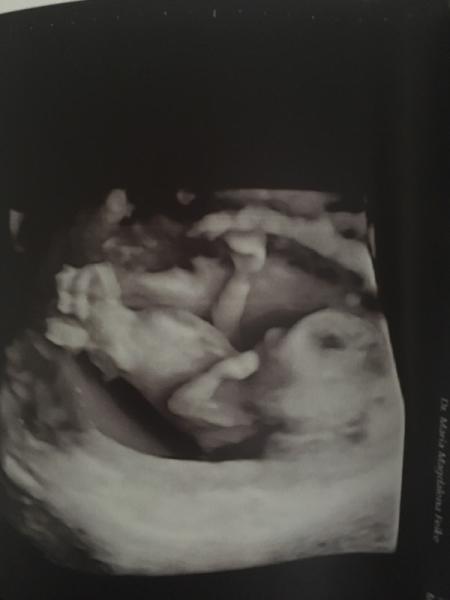

Hallo! Ich war heute beim Combine Test und es schaut alles gut aus. Der kleinen Erbse geht es gut und ist schon 7 cm groß. Die Ergebnisse von Bluttest bekommen wir am Mittwoch. Die FÄ hatte auch eine Tendenz zum Geschlecht. Bin Ende der 13. SSW. Habt ihr Erfahrung damit, wie sicher diese Tendenz ist? Liebe Grüße!

Bild zu Combine Test - Forum für April - Mamis

"Er" spielt an der Nabelschnur? < 3

Die kleine Erbse hat sich heute hinter allem versteckt, was es finden konnte..